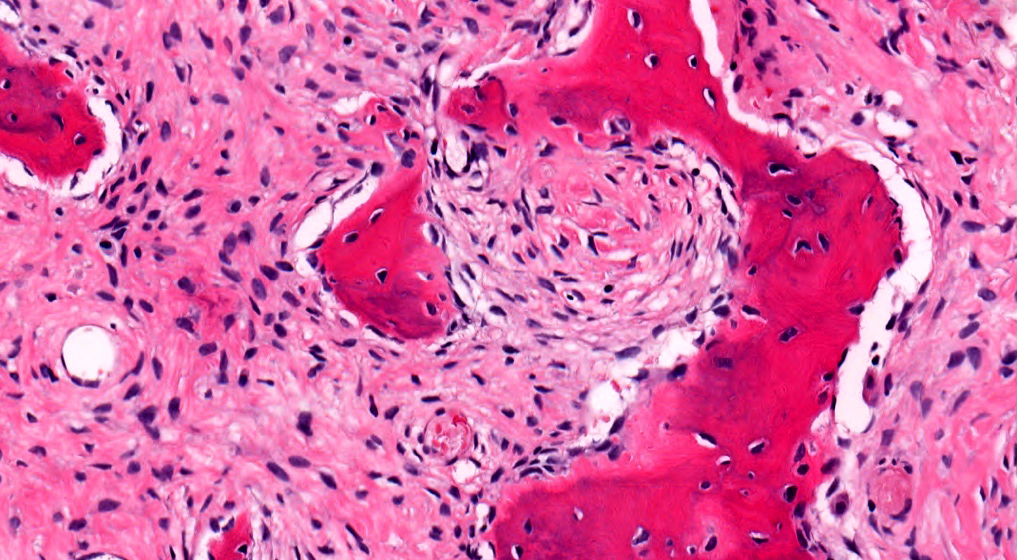

Microscopic (histologic) description

- Branching and anastomosing irregular trabeculae of woven bone ("C" and "S" shapes) with no conspicuous osteoblastic rimming

- No / rare osteoclasts

- Intervening fibrous stroma containing cytologically bland spindle cells, without prominent cytologic atypia

- Mitotic figures rare

- Stromal changes, including myxoid change and fatty metaplasia, may be seen in some cases (BMC Musculoskelet Disord 2003;4:20)

- Secondary aneurysmal bone cyst-like changes may also be seen (Turk Patoloji Derg 2018;34:234)

Microscopic (histologic) images